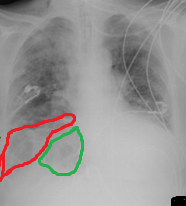

Προεγχειρητική (αριστερά) και μετεγχειρητική (δεξιά) ακτινογραφία θώρακος (Ευγενική παραχώρηση Dr. V. Penopoulos)